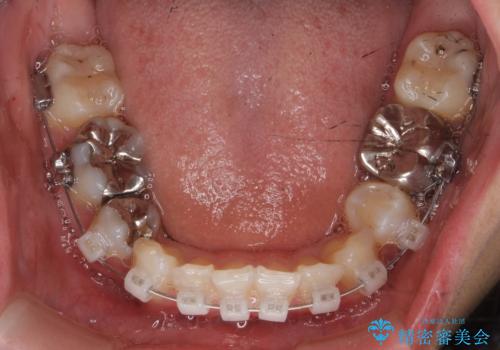

途中全体矯正をはさみ、根の向きが並行になった状態でブリッジを入れることができました。